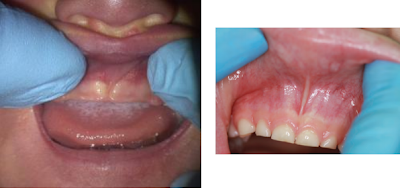

The quickest and easiest way to find out whether a baby has an upper labial tie is to lift up his upper lip and have a look!

Most babies will have no significant frenulum attachment(1).

Some babies will have a maxillary frenulum which attaches into the gum above the front teeth. This is not normally a problem, as there should still be enough upper lip mobility in order to achieve a good latch.

In some babies, the maxillary frenulum attaches just in front of the anterior papilla (that's the small bump of tissue on the upper gum just behind the area where the upper front teeth grow) (2).

Some babies (mine included) will have a maxillary frenulum which attaches into the papilla (the small bump of tissue just behind the area where the upper front teeth grow) and extends into the hard palate behind the front teeth (2).